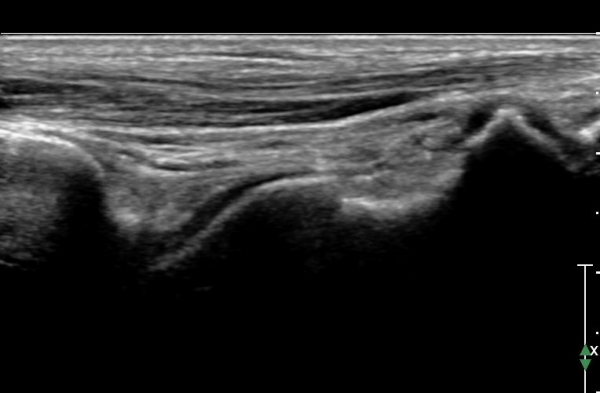

ÇϺΠ½ÅÀü ¶ì(inferior extensor retinaculum) ÀÇ frondiform Àδë Á¾´Ü¸é°Ë»ç¿¡¼­

frondiformÀÎ´ë ½ÉºÎ°¡Áö ÁÖº¯ ¼ö¾×Àú·ù°¡ °üÂûµÇ°í Á·±Ùµ¿ °æºÎÀδ밡 ³Ê¹« ¶Ñ·ÇÈ÷

°üÂûµÈ´Ù(»çÁø 5, 6, 7).